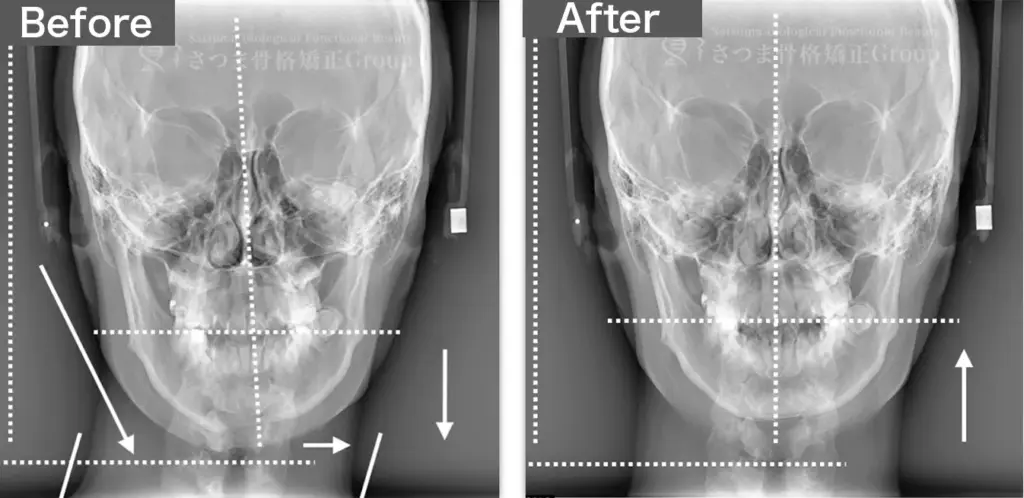

30代男性 リンタロー様

BEFORE

下顎やや左方シフト

下顎位の滑落

The mandible shows a slight leftward shift

with instability (slippage) of the mandibular position.

AFTER

中顔面の短縮

下顎の左方シフト改善、

正中誘導

下顎位の改善

整顔率の向上

correction of the leftward mandibular shift; guidance toward the facial midline; improvement in mandibular positioning; increased facial balance and symmetry.